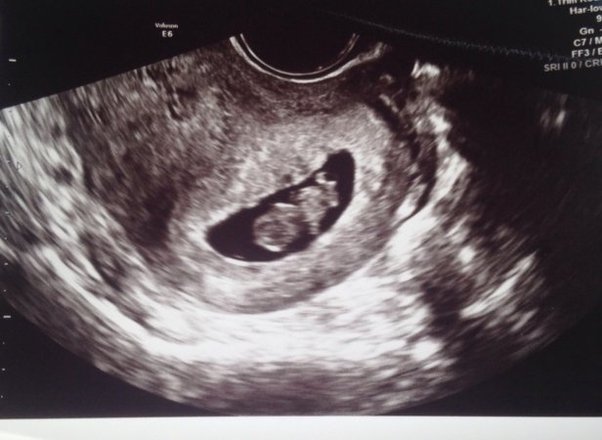

One recent study found that the ultrasound technician correctly predicted a baby's gender 98 percent of the time. An early second trimester sonographic indicator of fetal gender. If you want to know your baby's sex . If you are planning to do gender reveal ultrasound, this article can help to get better results during your ultrasound session. Gender predictions made by ultrasound have an accuracy rate north of 90 percent, carr said.

Still, the results of your . If you want to know your baby's sex . The accuracy of determining your baby's gender increases with how far along you are in the pregnancy. But mistakes can be made when determining gender . Gender predictions made by ultrasound have an accuracy rate north of 90 percent, carr said. An early second trimester sonographic indicator of fetal gender. It is obtained by looking at a profile view of the fetus (known as the midline sagittal plane). If you are planning to do gender reveal ultrasound, this article can help to get better results during your ultrasound session.

If you want to know your baby's sex . But mistakes can be made when determining gender . Still, the results of your . It is obtained by looking at a profile view of the fetus (known as the midline sagittal plane). An early second trimester sonographic indicator of fetal gender. Gender predictions made by ultrasound have an accuracy rate north of 90 percent, carr said. One recent study found that the ultrasound technician correctly predicted a baby's gender 98 percent of the time. This is something that can be identified on babies at this stage and . If you are planning to do gender reveal ultrasound, this article can help to get better results during your ultrasound session. The accuracy of determining your baby's gender increases with how far along you are in the pregnancy. The accuracy can vary from 70.3% at 11 .